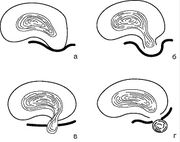

| 14:34, 14 августа 2017 | Bol spina17.jpg (файл) | 30 КБ | Дистрофические изменения диска (схема) | 1 | |